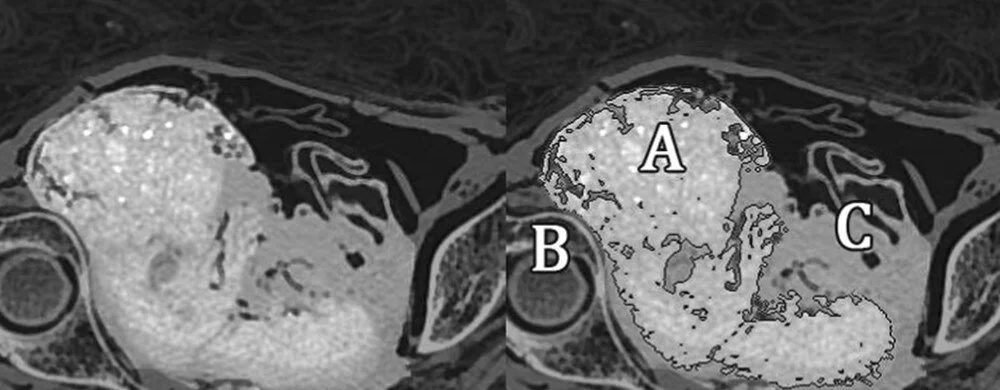

Polonya'daki Varşova Üniversitesi'nden araştırmacılar, geçen yılın Nisan ayında CT ve X-ray taramaları kullanarak doğmamış çocuğun kalıntılarının varlığını ortaya çıkardı.

Journal of Archaeological Science adlı bilimsel dergide yakın zamanda yayımlanan çalışmada mumya ile ilgili araştırmanın yeni bulguları paylaşıldı.

Bilim insanları, söz konusu kadın mumyasının içerisinde bir fetüs içeren ilk örnek olduğunu söyledi. Ayrıca mumyanın, Aralık 1826'da Varşova Üniversitesi'ne bağışlayan Jan Wężyk–Rudzki tarafından Mısır'dan satın alındığı aktarıldı.